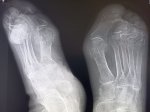

IMG20251014105834.jpg

Чо тут у нас?

>>325599083

Удар об угол дивана?

Аноним 16/10/25 Чтв 08:44:49 #9 №325599274

>>325599234

Ни, прост вальгусная деформация

IMG20251008112937.jpg

Плов я вчера доел, в вс приготовил, а от макарошек я с диетической целью отрекся не могу контролировать их поедание :-(

Аноним 16/10/25 Чтв 09:18:08 #26 №325600117